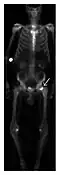

Proximal femoral fractures usually occur in osteoporotic patients, and their signs include subtle neck angulation, trabecular angulation, and subcapital impaction line. A frog-leg lateral view may be helpful if the greater trochanter is short enough. However, positioning can be difficult because of hip pain. In patients with strong suspicion of proximal femoral fracture and negative radiographs, MRI limited to coronal T1 W images and scintigraphy can be highly valuable (Figures 13 and 14). Such an option, with limited examination time, is cost-effective and allows reliable exclusion or confirmation of the diagnosis, preventing an unnecessary stay at the hospital or delayed treatment. Moreover, MRI helps to detect soft tissue abnormalities which are more frequently seen in femoral, acetabular, and pubic injuries than sacral lesions. Concomitant fractures are also frequently seen in typical pelvic sites.[1]

Figure 14: Subcapital insufficiency fracture in a 55-year-old man with a left hip pain without a history of trauma. Anteroposterior and Lauenstein view radiographs centered on the left hip do not show an obvious fracture line, but mild acetabular osteophytosis was noted consistent with hip osteoarthritis (not shown). (a) Coronal T1-weighted MRI shows a linear low-signal band through the femoral neck corresponding to a fracture line (arrowheads). (b) Bone scintigraphy shows focal uptake (arrow) corresponding to the fracture.[1]